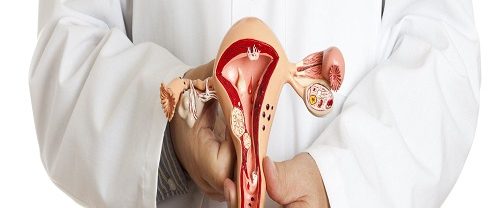

Ürojinekoloji Nedir? Ürojinekoloji, üroloji ve jinekoloji disiplinlerinin birleşiminden oluşan bir tıp dalıdır. Bu alan, kadın üreme sistemi ve idrar yollarıyla ilgili sağlık sorunlarını inceleyen ve tedavi eden bir uzmanlık alanıdır. Kadın anatomisi gereği idrar yolları ve üreme organları birbirine yakın olduğundan, bu alan iki farklı tıp uzmanlığının kesişim noktasında yer alır. Ürojinekolojinin Kapsamı Ürojinekoloji, kadınların…

Myomektomi Nedir? Myomektomi, rahimdeki miyomların cerrahi olarak çıkarılması işlemidir. Miyomlar, rahim duvarının kas dokusundan oluşan benign (iyi huylu) tümörlerdir. Bu tür tümörler genellikle kadınların üreme çağında görülür ve genellikle hormonlarla ilişkilidir. Miyomlar, adet döneminde artan kanama, ağrı ve pelvik baskı gibi semptomlara neden olabilir. Büyük veya belirli bir konumda bulunan miyomlar ayrıca hamilelik sırasında komplikasyonlara…

Kadın İnfertilitesi Nedir? Kadın infertilitesi, bir kadının istediği şekilde bir çocuk sahibi olamama durumudur. İnfertilite, genellikle bir yıl boyunca düzenli cinsel ilişkiye rağmen hamilelik elde edilememesi olarak tanımlanır. Kadın infertilitesi, çeşitli faktörlerden kaynaklanabilir ve üreme sistemine yönelik çeşitli sorunları içerebilir. Kadın İnfertilitesinin Nedenleri Nelerdir? Kadın infertilitesinin çeşitli nedenleri olabilir. Bunlar arasında şunlar bulunur: Yumurtalık sorunları:…

Histerektomi Rahim Alınması Nedir? Histerektomi Rahim Alınması, bir kadının rahminin tamamen veya kısmen cerrahi olarak çıkarılması işlemidir. Bu prosedür, çeşitli sağlık sorunlarına çözüm olarak uygulanabilir. Rahmin alınması, genellikle aşağıdaki durumlar için gereklidir: Rahim Kanseri veya Prekanseröz Durumlar: Rahim kanseri teşhisi konulmuş veya rahim hücrelerinde kanser öncüsü değişiklikler tespit edilmişse, histerektomi tedavi seçeneklerinden biri olabilir. Myomlar…